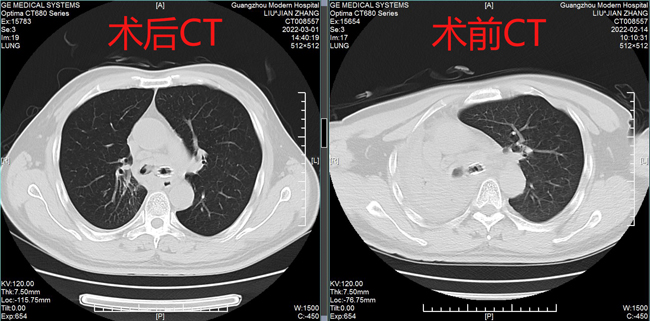

术前术后CT表现

据黄德良主任介绍,刘健患者这次因肺鳞癌引起气喘问题过来求治的。入院后经过完善检查诊断为右肺鳞癌并胸膜、肺门、纵膈淋巴结转移,已是T4N2M1属于肺癌IV期了。“当时情况非常紧迫,患者右主支气管主干完全堵塞,左主支气管堵塞,虽然之前在外院做了支架,但支架近端也有肿瘤导致大部分的堵塞。病人呼吸困难,经皮血氧低于80%。在麻醉科,气管镜室和8楼医护共同努力下给病人行右主支气管肿物微波消融术,术后气道恢复通畅,右肺完全复张!患者手术中还出行反复出血,情况非常不理想,幸得患者家属无条件的信任,经过团队的共同努力,历时3个多小时的手术还是顺利完成。目前病人已经可以下床走路,经皮血氧恢复至95%。”2月15日,经过黄教授团队的评估后,患者接受了介入化疗方案,术后患者呼吸困难症状得到进一步改善,指尖血氧好转。在2月20日再次接受气管镜下双侧主支气管肿物微波消融术。3月1日复查了CT,患者肿块缩小,右肺复张。